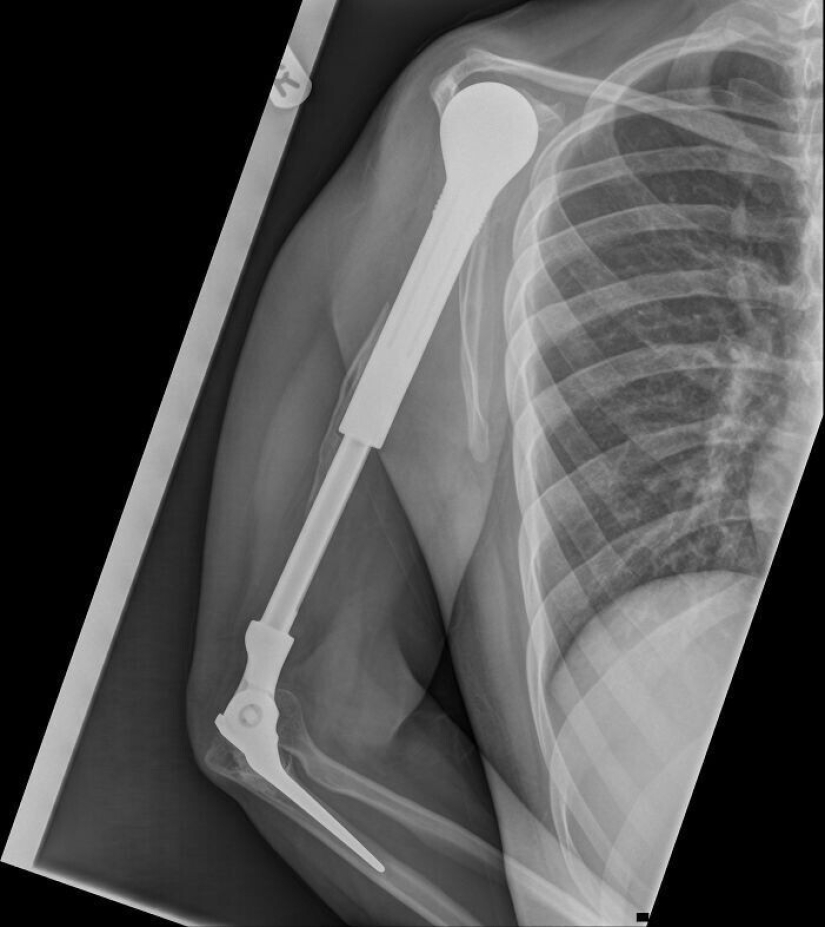

"Eso es x-ray en mi metal manos"